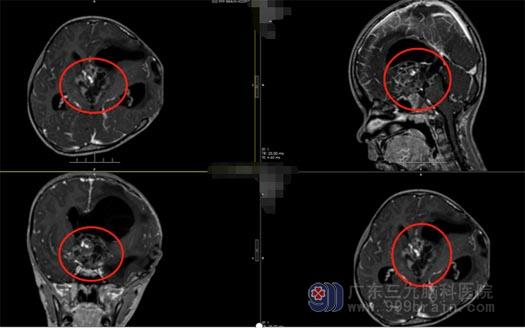

“初次见到嘉嘉,她很乖,不哭不闹,问她的问题都能自己回答,但看起来较同龄孩子瘦小很多,精神倦怠,让我非常心疼她,当时就想一定要尽最大的努力帮助她”,鲁明了解孩子的情况后,考虑不仅仅是单纯的脑组织膨出,马上安排磁共振检查,结果显示:1.鞍上、三脑室巨大占位;颅咽管瘤?;2.梗阻性脑积水3.左侧额颞部颅骨缺损。